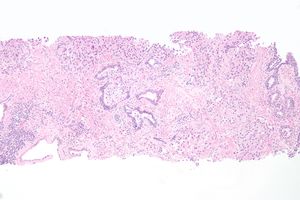

요도 벽의 구조는, 안쪽에 점막이 있고, 바깥쪽에는 주로 2층의 평활근이 존재하는 것이 기본이지만, 남성의 요도해면체 내에서는 평활근층이 명확하지 않다. 요도 내부 벽의 윤활제로서 점액을 분비하는 '''요도선'''이라고 불리는 소형 분비선이 다수 존재하며, 요도의 내벽을 적시고 있다. 안쪽의 점막은, 여성의 경우 방광의 아주 가까운 곳에서는 방광과 같은 이행 상피이지만, 그 외의 대부분은 중층 편평 상피이다. 남성의 경우 방광 근처에서는 이행 상피, 그 후, 전립선 내를 통과할 때는 전립선의 상피와 유사한 다열 원주 상피가 되며, 음경 내에서는 독특한 중층 원주 상피, 귀두부에서는 중층 편평 상피로, 다양하게 형태를 바꾼다.

요도를 덮고 있는 상피는 방광을 빠져나올 때 이행 상피로 시작한다.[17] 요도 안쪽으로 더 들어가면 거짓 중층 원주 상피와 중층 원주 상피가 나타난다.[17] 요도 끝 부분 근처에서는 중층 편평 상피로 바뀐다.[17]소량의 점액을 분비하는 요도선과, 요도를 윤활하는 점액을 분비하는 쿠퍼선(구요도구선)이 있다.[17]